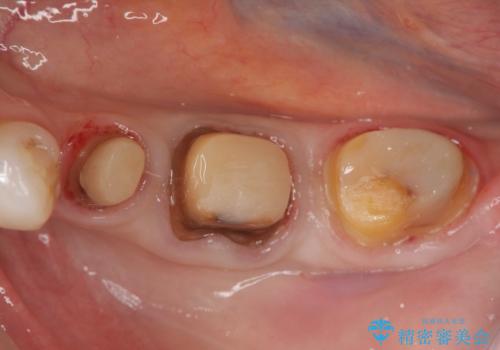

- 違和感や疼きのある左側小臼歯に加え全体的にクラウンや詰め物のやりかえを希望され来院されました。

治療後に再発した虫歯や根管再治療に加え、穴の空き症状のある上顎左側小臼歯は抜去を行いインプラントによる機能回復治療を計画します。

X線写真検査ではわからない虫歯も外してみると再発していることがあります。虫歯を丁寧に取り除き、再発を防ぐべく精密なクラウンの作製を行うことが長期的な予後につながります。